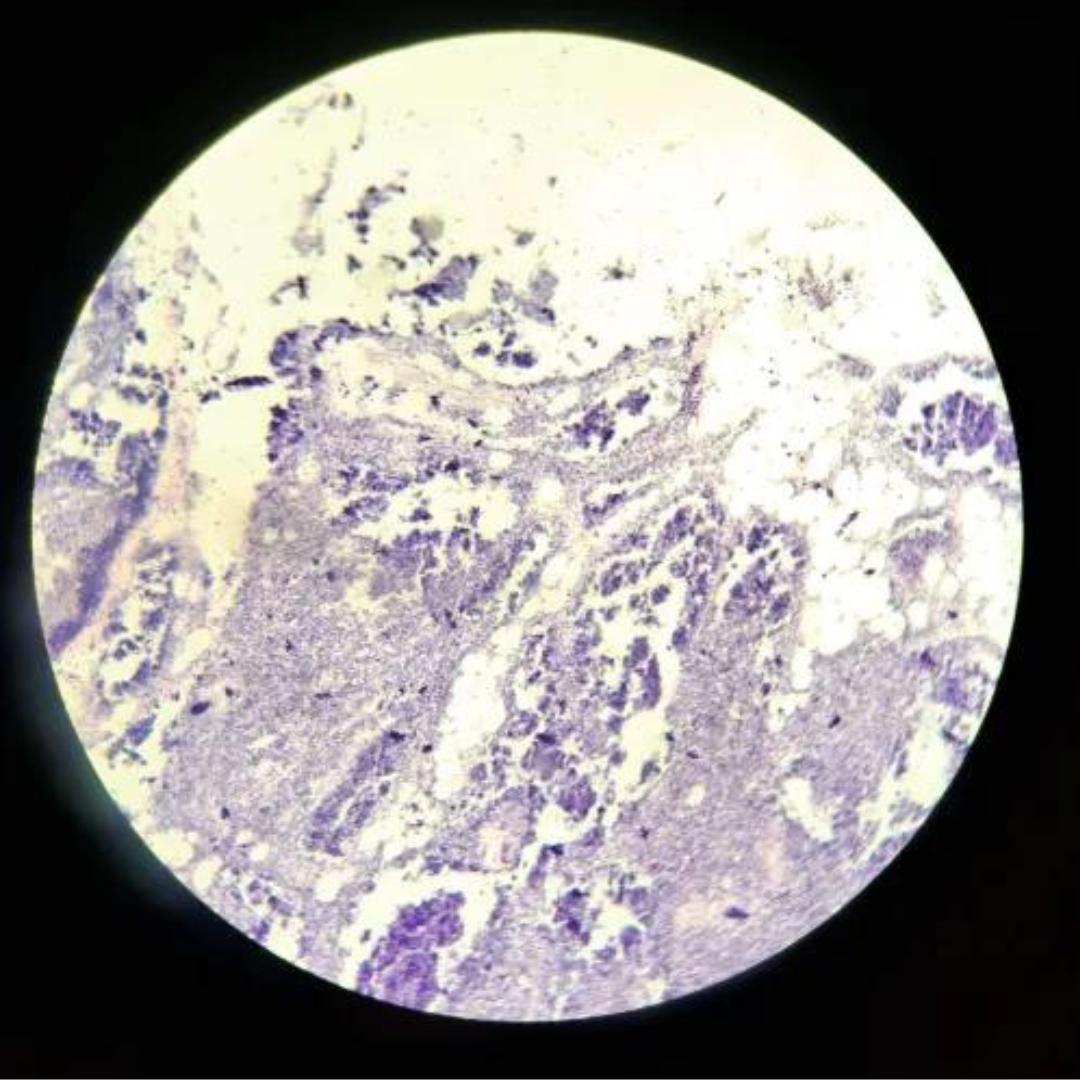

Spleen

Spleen

Spleen

Spleen

Spleen

Spleen

Spleen

Spleen

Spleen